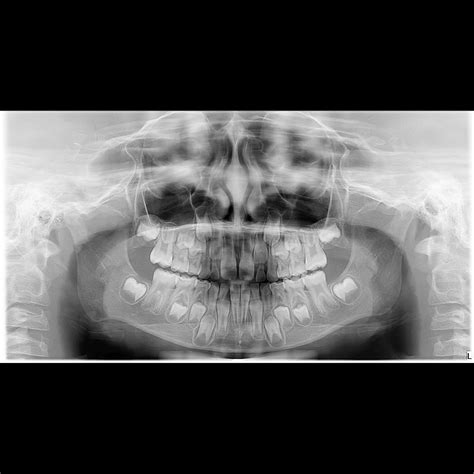

La prova della struttura in bocca al paziente conferma la passività e il preciso accoppiamento, sia clinicamente che radiograficamente.

La protesi viene consegnata in studio e montata in bocca seguendo il protocollo di serraggio delle viti, con torque crescente e alternato. Viene eseguita una radiografia di controllo finale, e la paziente viene seguita con appuntamenti periodici.